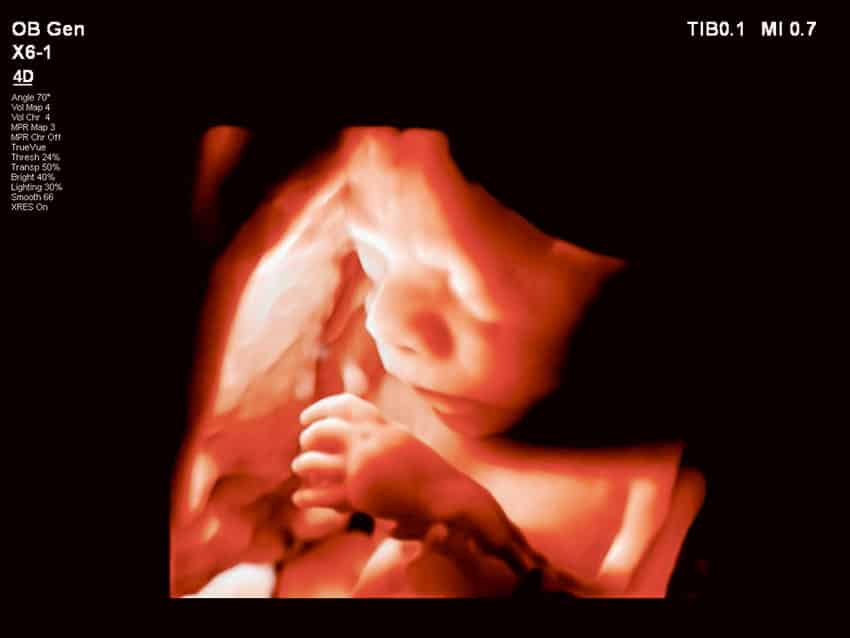

• Baby With Spina Bifida Was Removed From Her Mother’s Womb for Surgery Then Put Back In